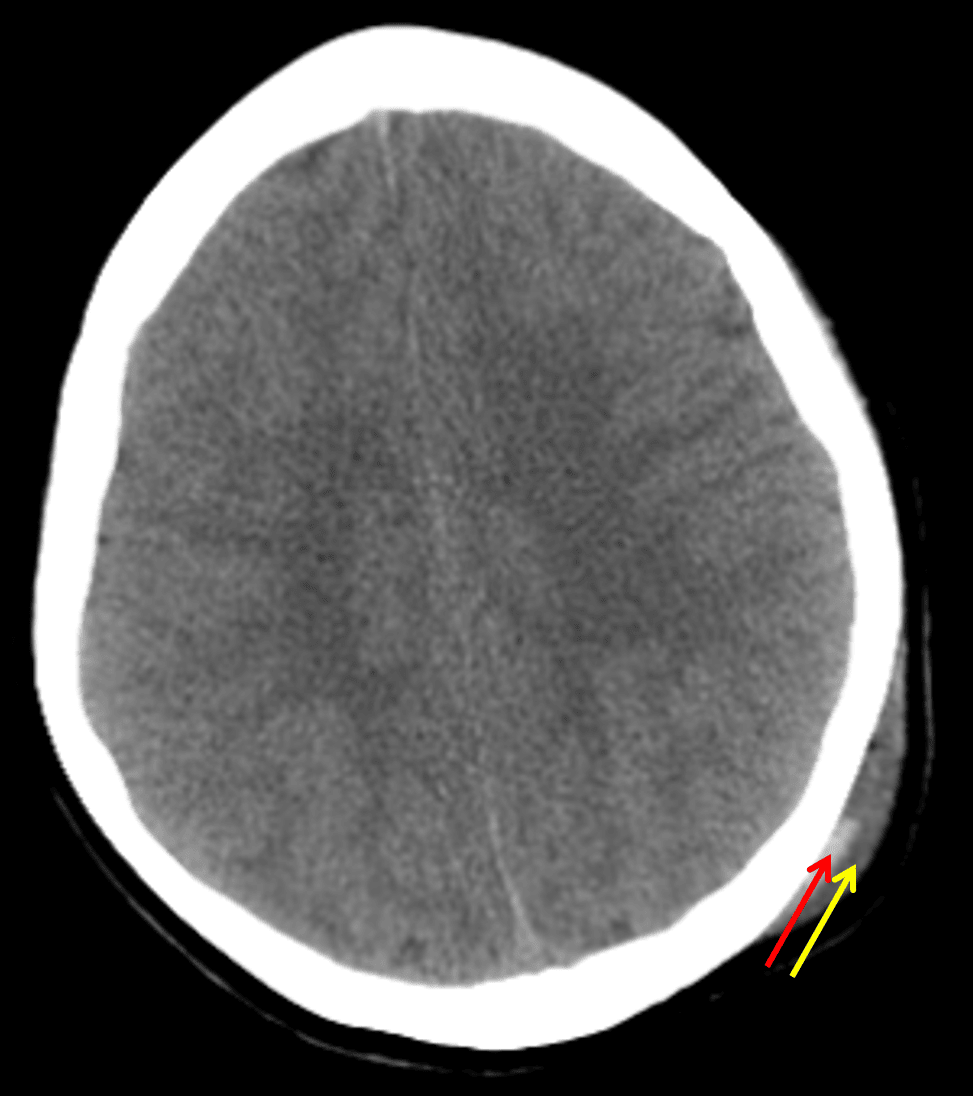

Scalp hematoma with distinct deep (red arrow) and superficial (yellow arrow) components. The deep component contains layering hyperdense blood products and is likely subgaleal in location.